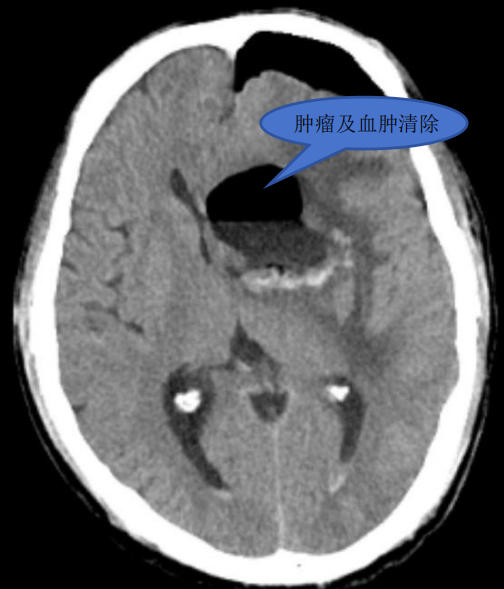

手术由王继斌副主任、罗绳祝主治医师、杨志医师,联合麻醉手术科团队共同完成。术中,王继斌副主任利用神经内镜的抵近观察优势在内镜下沿肿瘤边缘逐步、仔细的分离脑肿瘤,最终将肿瘤全切,同时清除颅内血肿。术后患者麻醉清醒、言语正常、四肢活动正常。

术后影像